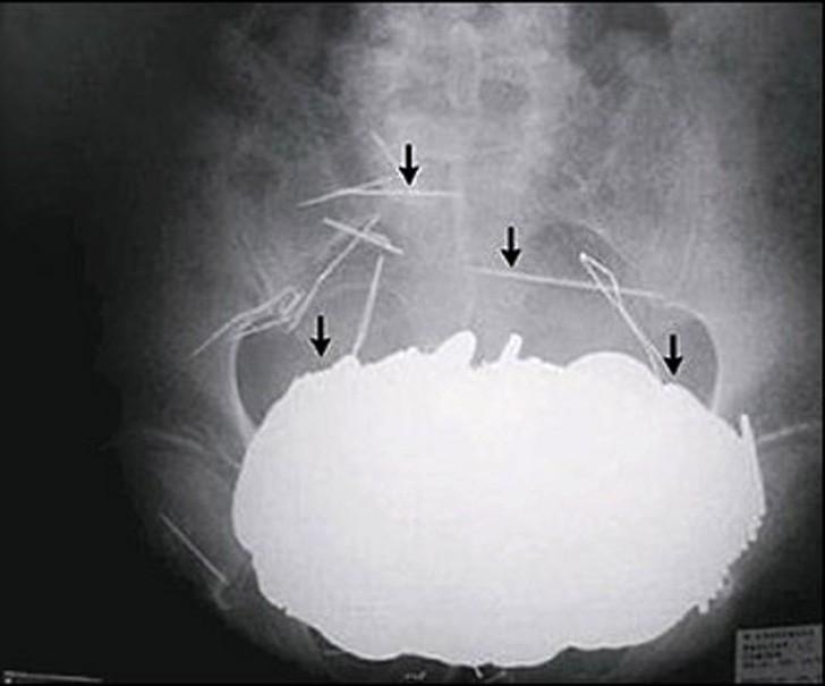

Pinzas.